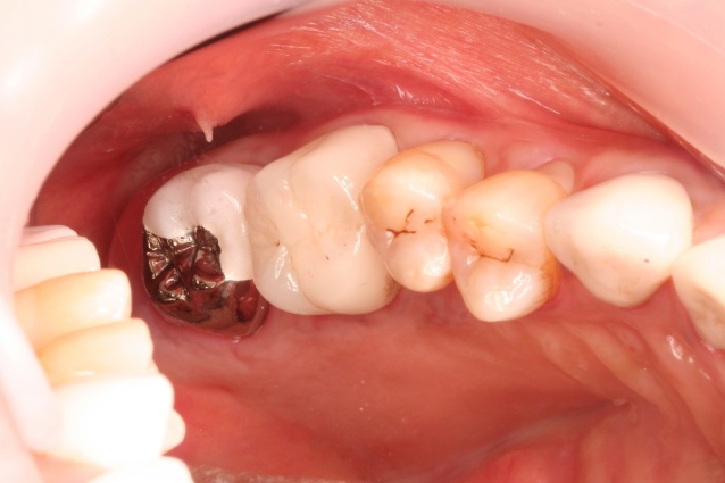

インプラント

担当歯科医師:佐藤英司

2013年5月3日千葉市若葉区 Y.T様 左下6番 インプラント上部構造